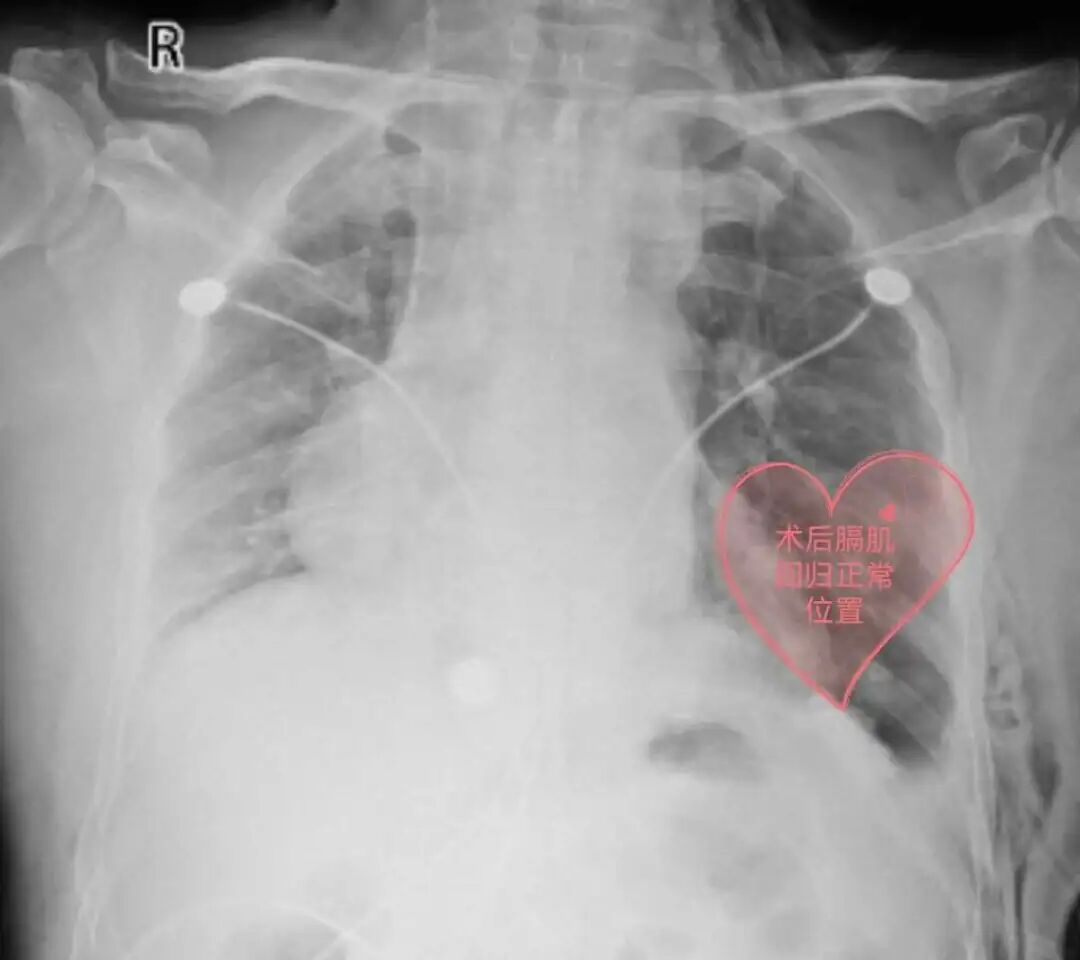

近日,家住遵义的一名55岁患者李某,因活动后喘累、气促多年,辗转多家医院就诊无果,终于在贵州航天医院成功治疗。 病情回顾 几年前,李先生爬坡上楼就开始有点喘累、呼吸急促,但是自己并未引起重视。 第一次入院贵阳某三甲医院 1年前,李先生症状加重,爬到2楼中途都需要缓口气休息,于是到当地某大型三甲医院就诊,入住心血管内科,做了心脏血管造影、心脏彩超、胸部CT、抽血化验等很多检查,住院两周,医生告诉他心脏没什么大问题,仅是左侧胸腹腔之间的膈肌位置有点抬高,心脏位置有些右偏,属于先天异常,无需治疗,随即李先生办理出院。 第二、三次辗转贵阳某三甲医院 李先生的症状仍没有得到缓解,又先后辗转到贵阳市2家三甲医院就诊,同样诊断为膈膨升症,两家医院均未给出缓解症状和治疗的合理方案,于是李先生又开始继续寻医之路。 西南医院医生推荐 贵州航天医院 热心邻居向他推荐去西南医院,在咨询该院医生后,医生建议李先生“不用跑这么远,到贵州航天医院一样可以治疗”。 李先生来到贵州航天医院门诊,刚好遇上心胸外科陈光春主任坐诊专家门诊,陈主任听闻李先生的病情后,详细介绍了膈膨升症的相关问题,并告诉他手术后的效果,为他仔细分析病情,告诉他“心脏虽然位置有些右偏,但心功能是正常的,不会影响手术效果”。 入院后第4天,心胸外科团队经过充分的术前准备,在全麻下为李先生行电视胸腔镜微创膈肌折叠缝合术,术后各项指征恢复正常,顺利出院。出院后,爬坡上楼再也不累了、不喘了,一口气走上4楼也没问题。 为此,李先生感叹历时1年多,走了这么多家大医院,最终选择在贵州航天医院就诊,无论是门诊、手术室,还是住院部、辅助检查科室,医护人员服务态度都非常好,解释病情也非常耐心仔细,让人感觉非常专业非常有水平,所以才决定就在贵州航天医院手术治疗,治疗效果也证实自己的选择是非常正确的。 在医院的晨读会上心胸外科就介绍过“膈膨升症”疾病的知识,以及采取的微创手术治疗效果。此次李先生首次挂号的并非心胸外科,而是挂的呼吸科,因呼吸科的门诊医生听患者自我阐述在其他医院诊断是膈膨升症,呼吸科医生立即带患者到心胸外科门诊就诊。 贵州航天医院每周三举行的“晨读会”,通过不同学科、不同专业的讲解汇报,拓展医院各层级医务人员的知识结构,解决临床遇到的难点和问题,凝聚发展合力,以医院晨读会推动各科室形成常态化学习机制,营造全院比学赶超良好氛围,进一步提升医疗服务质量,以“小进步”促进“大发展”,为健康遵义建设贡献医院力量。 科 普 什么是膈膨升症? 膈膨升症被称为膈肌膨出症,属膈肌无力类疾病,膈肌活动强度减弱,包括膈肌麻痹和膈肌膨出症。 狭义的膈膨升症是指:由于胚胎横中隔内肌肉组织发育异常,导致膈肌先天性缺陷引起的膈肌膨出,称为先天性(或原发性)膈膨升症。 广义的概念通常被用来指膈肌纤维因发育不良、萎缩而异常的抬高,包括膈神经的不明病因、不明部位的损伤造成的膈肌抬高,称为获得性(或继发性)膈膨升症。 膈膨升症应该如何治疗? 膈膨升症只有在产生症状时才具有临床治疗意义,原因如下: (1)药物不能控制的呼吸功能衰竭; (2)伴胃肠道梗阻症状时; (3)不能与肿块膈疝鉴别的病例。 1947年Bisgand首次对膈膨升症进行了手术治疗并获得成功,其关键是通过手术阻止膈肌继续上移和消除矛盾运动。手术方法是膈肌折叠术,包括膈肌不切开折叠法膈肌切开折叠法和膈肌部分切除后的对端褥式缝合法。 近年来多采用电视胸腔镜微创膈肌折叠术,其膈肌折叠法因为能在电视屏幕直视下缝合避免损伤膈下脏器而更加安全可靠。电视胸腔镜手术治疗效果满意,创伤较传统开胸手术轻微,手术并发症及死亡率很低。术后患者动脉血氧分压和氧饱和度显著提高,通气功能明显改善,活动后气促等症状明显改善甚至消失。 贵州航天医院心胸外科简介 心胸外科是诊治疾病种类较为复杂,专科性非常强的一门学科。心胸外科手术难度大,风险高,对设备和配套要求也高,大众对心胸外科经常会存有误解,误认为心胸外科只是看胸外面的病,这就很容易让人联想到乳腺疾病等,其实胸外科主要看的是胸腔内的病,主要是食管、气管及肺上的疾病。如食管囊肿、食管平滑肌瘤、贲门失迟缓症、严重的反流性食管炎、食管裂孔疝、自发性食管破裂、食管、气管瘘、食管癌、食管胃交界处癌(贲门癌)、肺大疱(有时破裂引起自发性气胸)、肺脓肿、肺隔离症、肺结核球、肺结节等需到心胸外科就诊。 心胸外科导航 贵州航天医院呼吸综合楼003诊室 住院病区:呼吸综合楼4楼 门诊坐诊时间 每周一至周五 (08:00—12:00; 14:00—17:00) 咨询电话 住院病区咨询电话:27677360(医生办公室);0851-27677732(护士站) 心胸外科专家